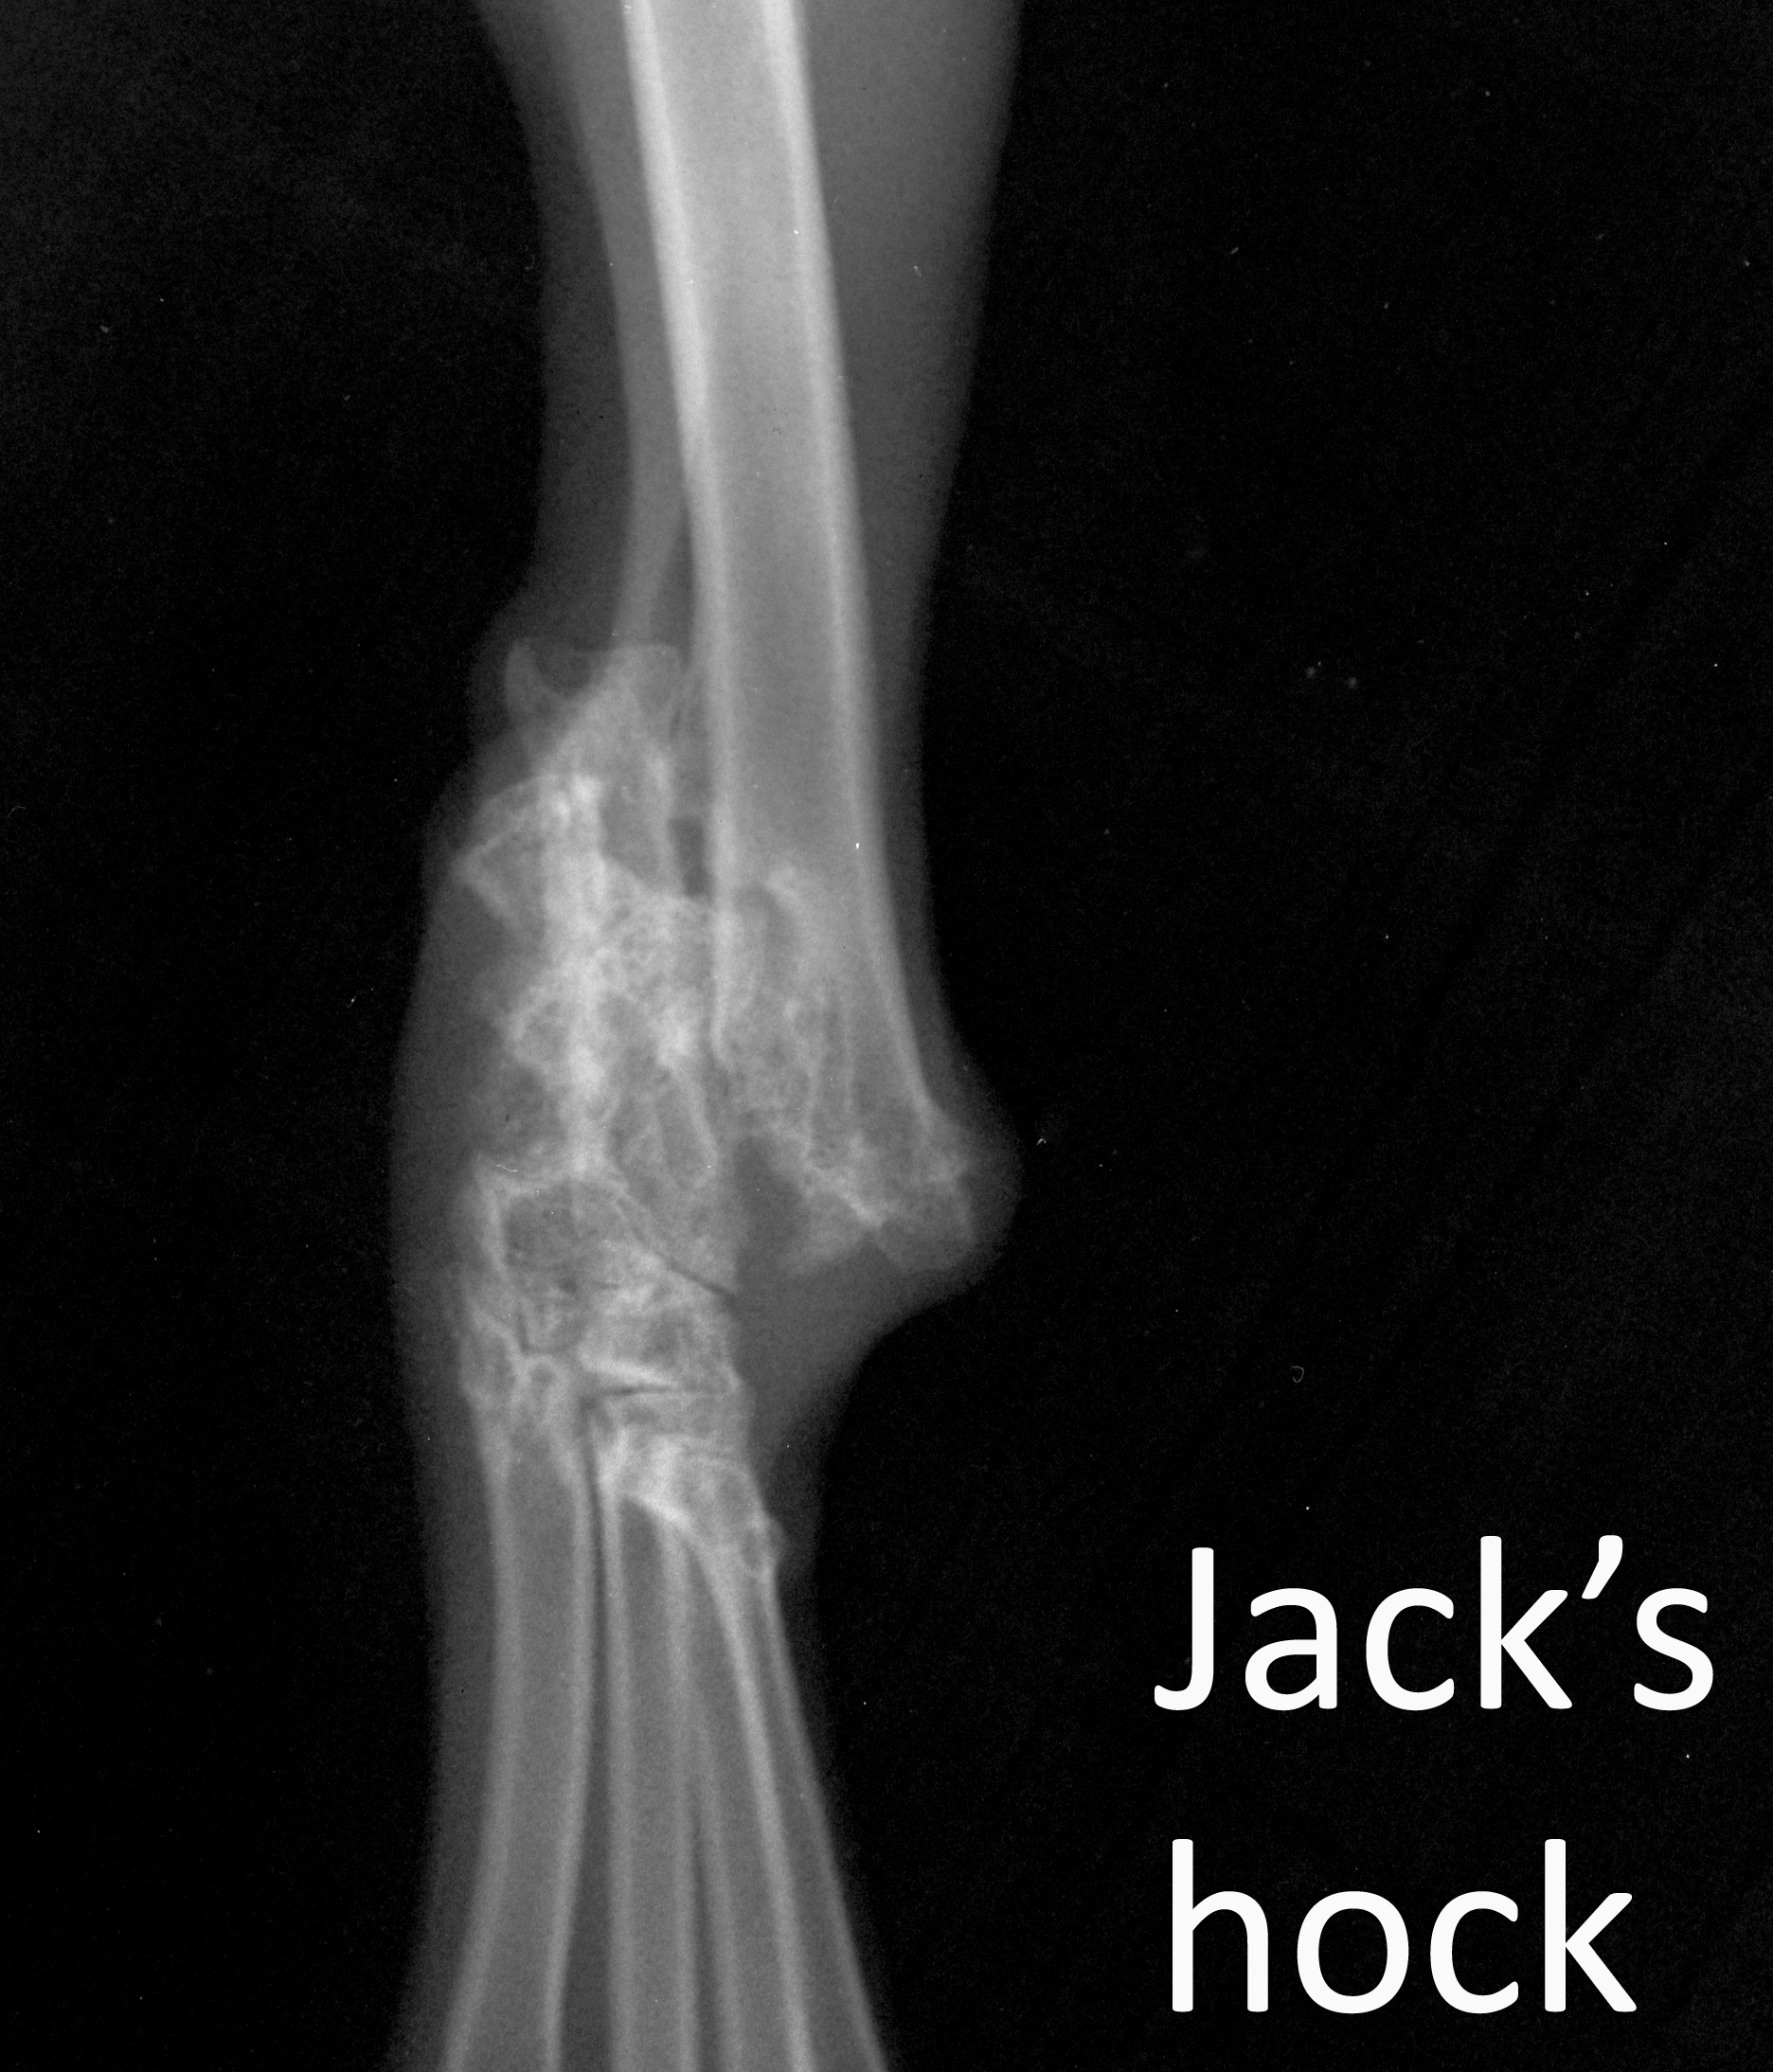

Jack's hock

Labelled image of Jack's hock VD

Filed under:

Radiograph

Orthopaedics